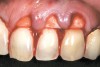

The 2.5-week postoperative clinical view can be seen in Figure 10 through Figure 12. Note the rapid soft tissue healing and maturation. At 6-weeks postoperative, tissue plasty was accomplished to blend the thickened keratinized tissue, in addition to placement of class V composite restorations at teeth Nos. 5, 6, and 11 to create a new restorative margin on the root surfaces.

The 2-month postoperative view can be seen in Figure 13 through 15. Note the color match of the tissue, balance of the facial heights of contour, and zones of attached keratinized tissue present.

Figure 10  Case One The 2.5-week postoperative view, maxillary anterior.

Figure 10